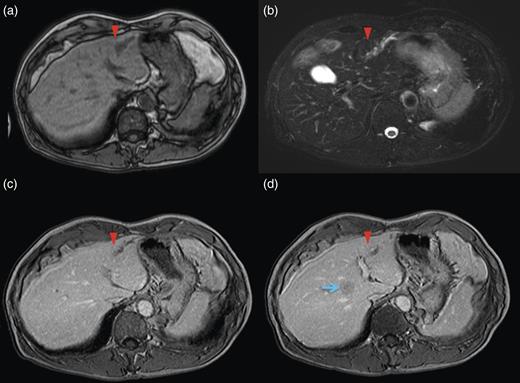

Computed tomography (CT) demonstrated two solitary lesions in segment (S) eight. Furthermore, S3 hepatic duct dilatation was clearly detected on CT scanning (Fig. 1).